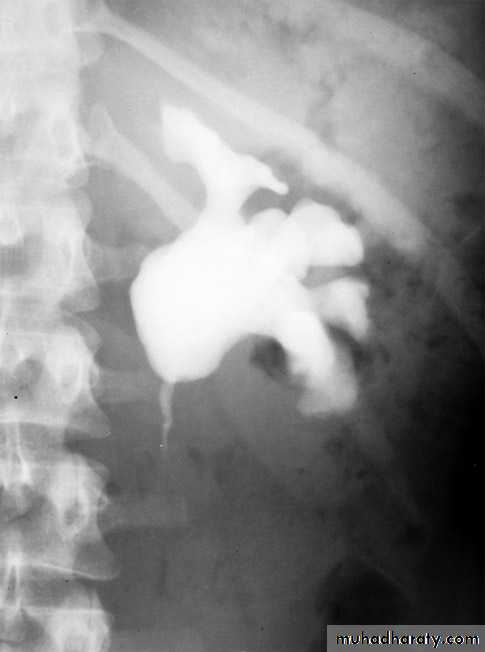

IVU :

- There is rounded or elliptical dilatation of lower end of ureter with thin linear filling defect around it , resembling (cobra head appearance),

- Proximal dilatation of rest of ureter .

- In advanced cases hydronephrosis .

- In obstructed ureterocele , filling defect in the bladder